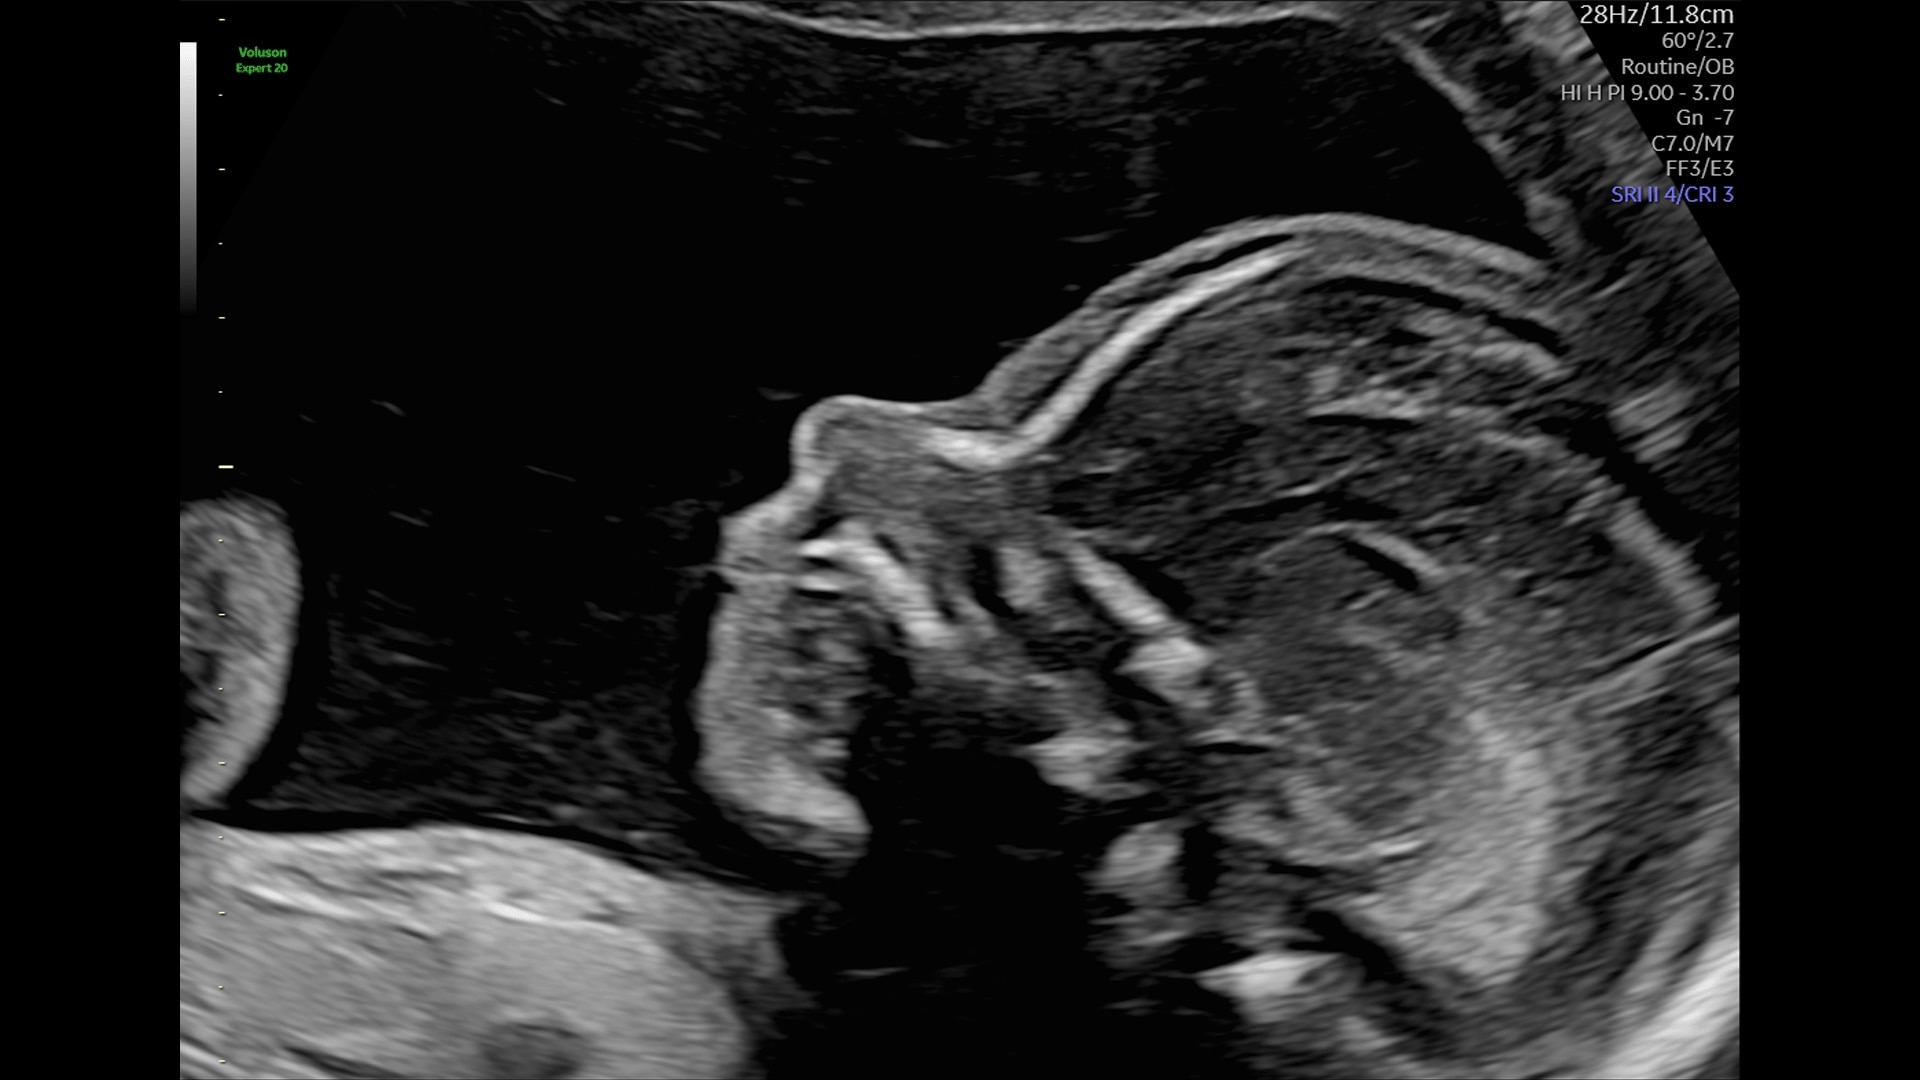

Generate spectacular 2D/3D and color Doppler images with increased penetration and stunning clarity, to help visualize critical details needed for diagnostic assurance. The Lyric Architecture unlocks new imaging and processing power to expand your imaging capabilities for years to come